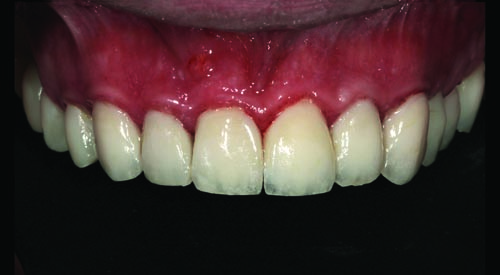

Fig. 2: Close-up retracted facial view of the patient’s upper and lower arches reveals extensive decay, missing teeth and obvious gingival inflammation.

Fig. 33: Close-up retracted postoperative view of the definitive maxillary restorations, which included IPS E.max onlays, crowns and veneers.